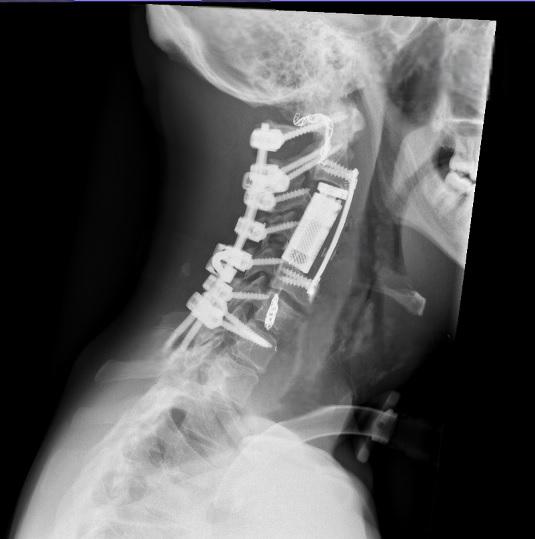

وفي المرحلة الجراحية، تم إجراء تثبيت خلفي للعمود الفقري من الفقرة العنقية الأولى وحتى السابعة، مع تحرير النخاع الشوكي وتأمين استقرار الفقرات، وبعد ذلك، أُجري استئصال كامل للورم والفقرات المصابة بطريقة “الاستئصال الكامل في كتلة واحدة” عبر المدخل الأمامي للعنق، تلاه تعويض الفقرات باستخدام قفص فقري تمددي، مع تثبيت أمامي لضمان الثبات الكامل للعمود الفقري.

وأكد البربراوي أن هذه العملية تُعد الأولى من نوعها في الأردن والمنطقة، ولا تُجرى إلا في المراكز المتقدمة على مستوى العالم، نظرًا لتشريح الورم المعقد، إذ شملت استئصال أكثر من فقرة عنقية إضافة إلى الشريان الفقري المصاب المجاور للورم.